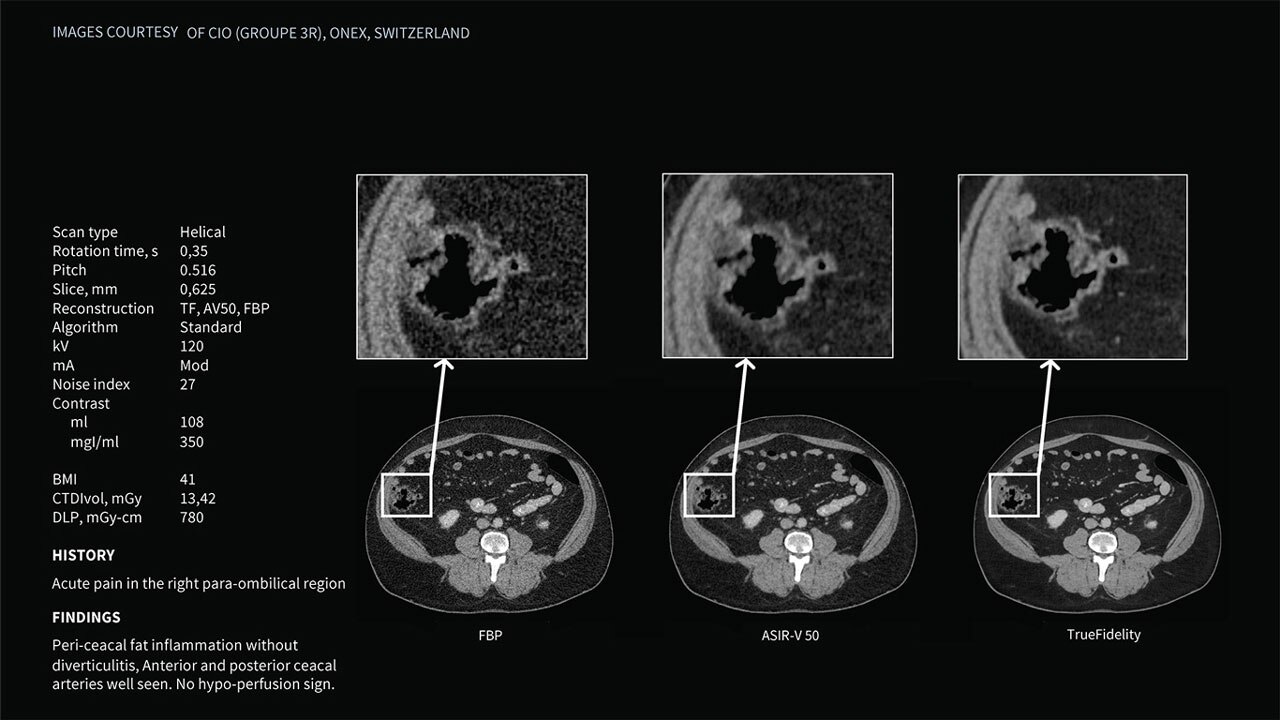

Deep learning image reconstruction, higher special resolution at 0.23 mm